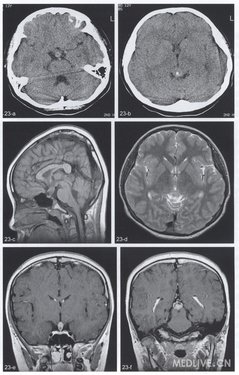

男,12岁。性早熟、视力减退2年、尿量增多半年。体检:双眼上视受限、双眼颞侧视野缩小。实验室检查尿比重降低。

CT平扫(图23a,b)示鞍上池与松果体区各见一结节状稍高密度结节,最大径分别为1.3cm与1.9cm,松果体区肿块包绕松果体钙化并压迫第三脑室后部。MRI(图23c,d):上述肿物呈T1WI稍低信号及T2WI等信号,矢状位显示鞍上区肿物祟及漏斗和垂体柄,增强T1WI(图23e,f)肿块大部明显强化,鞍上肿块下部及松果体区肿块上部强化不明显。

(鞍上肿块手术)生殖细胞瘤。

特征为松果体区肿块包绕松果体及鞍上肿块,伴尿崩。CT为边缘清楚的稍高密度肿块,位于第三脑室后方的松果体区者包绕松果体钙化(如本例)或使之破坏。位于鞍上者见于视交叉后方,无囊变与钙化。增强扫描一般强化显著及均匀。但较大肿瘤、尤其是位于基底核一丘脑区者常可见囊变、坏死及出血,因此密度不均匀。MRI检查肿瘤信号缺乏特征性,各序列上信号强度近似脑皮质,偶见T1WI高信号及T2WI低信号。T1WI-般与灰质等信号或稍高信号。T欧式I为等至高信号,等信号原因是肿瘤细胞密集及核质比大。FLAIR序列肿瘤信号稍高于脑灰质。T2*WI及SWI上钙化及出血为低信号。DWI上因水分子扩散受限而呈高信号。增强T1WI显示肿瘤均匀及明显强化。MRS显示Cho峰增高、NAA峰下降,伴或不伴Lac峰增高。松果体生殖细胞瘤还可侵犯第三脑室,导致脑脊液播散,增强扫描可见室管膜与脊膜增厚与结节状强化。

青少年松果体区与鞍上区肿块,伴视力改变、尿崩及性早熟者首先考虑生殖细胞瘤,CT可显示肿瘤包绕松果体钙化,但MRI对鞍上肿瘤及脑脊液轴肿瘤播散显示更好。本病对放疗极其敏感。